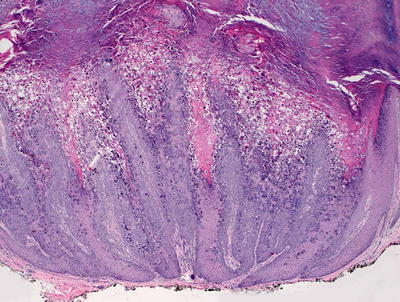

12.9.2 Histology

Histologic changes include a lobular proliferation of keratinocytes that contain eosinophilic cytoplasmic inclusions with a very characteristic appearance (Figs. 12.11 and 12.12). The inclusions begin in suprabasilar keratinocytes, and become progressively larger and more basophilic with upward progression in the epidermis. The epidermis is acanthotic with variable amounts of spongiosis. Transepidermal elimination is seen in many cases. An intense inflammatory response is present, and this is accentuated following rupture of the lesions. In some cases, atypical CD8+ lymphocytes and CD30+ cells are present within the infiltrate, leading to concern for lymphoma [10, 87]. Similarly, an intense inflammatory response has been identified in patients with altered immune systems [88]. Follicular involvement is commonly seen in immunosuppressed patients [4, 89].

Fig. 12.11

The epidermis is acanthotic and has a lobular appearance with abundant viral inclusions within keratinocytes in molluscum contagiosum

Fig. 12.12

Eosinophilic viral inclusions are present in keratinocytes and extruded at the epidermal surface in molluscum contagiosum